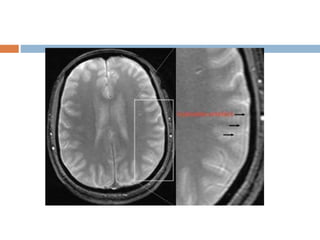

Aliasing artifact or

wraparound

 It occurs when the dimensions of the body part

being imaged exceed the FoV.

 The part beyond the FoV is projected to the

other side of the image.

 It is caused by under sampling in the phase

encoded direction.

 Choosing an FoV that is smaller than the area

imaged leads to wraparound or aliasing

artifacts.

 Appearance

 signals from outside the FoV seen in the

imaging volume.

 Solution

 Larger FoV and oversampling

 Use saturation bands outside the FoV.

Aliasing artifact or wraparound It occurs when the dimensions of the body part being imaged exceed the FoV.  The part beyond the FoV is projected to the other side of the image.  It is caused by under sampling in the phase encoded direction.  Choosing an FoV that is smaller than the area imaged leads to wraparound or aliasing artifacts.

 Appearance  signalsfrom outside the FoV seen in the imaging volume.  Solution  Larger FoV and oversampling  Use saturation bands outside the FoV.